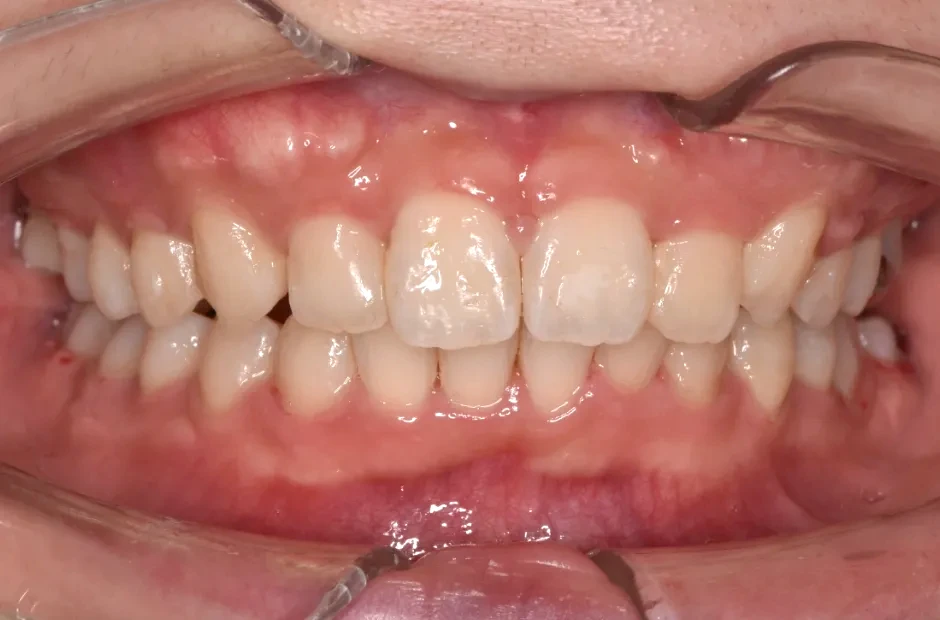

八重歯・でこぼこ・乱ぐい歯

(叢生)

歯が並ぶスペースが足りないために、歯が重なったり前後にずれて生えていたりする状態です。犬歯(八重歯)など目立つ部分の歯列が乱れている場合は、口元の印象に悪影響を与えます。原因としては、遺伝や乳歯の早期抜歯、顎の成長不足などがあげられます。歯磨きが不十分になりやすく、虫歯や歯周病のリスクが高まりやすい不正咬合です。矯正治療を受けると、見た目がよくなるだけでなく清掃性が高まり、お口の健康を維持しやすくなります。

叢生

| 診断名・主訴 | 叢生 |

|---|---|

| 年齢・性別 | 43歳・女性 |

| 治療期間・回数 | 2年7か月 27回 |

| 治療に用いた主な装置 | 舌側矯正 |

| 抜歯部位 | 両顎4,4 |

| 治療費 | 100万円(税抜) |

| リスク・副作用 | 装置による違和感・疼痛・歯肉退縮・歯根吸収・虫歯のリスクなど |

治療前